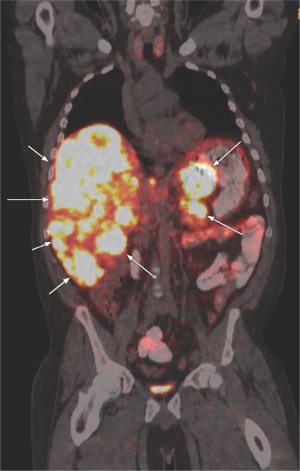

The patient subsequently presented to medical oncology clinic at our center, where examination was notable for right heart failure with jugular venous distension, a murmur of tricuspid regurgitation, and lower extremity edema; carcinoid syndrome with tachycardia, hypertension, and diaphoresis; and liver metastasis with extensive hepatomegaly. Labs were notable for an elevated serum Chromogranin A 1,430 ng/mL, serotonin 2,640 ng/mL, and random urine 5-HIAA 684 mg/g creatinine. Gallium DOTATE positron emission tomography (PET) demonstrated avid pancreatic tail primary and bulky, bilobar liver metastases with abdominal lymphadenopathy (Figure 2). These findings were consistent with a well-differentiated serotonin-producing PaNET G3, metastatic to liver and lymph nodes. Somatic tumor sequencing with the Memorial Sloan Kettering-Integrated Mutation Profiling of Actionable Cancer Targets (MSK-IMPACT) next-generation sequencing (NGS) for 505 genes revealed a microsatellite stable tumor with low tumor mutation burden (0.8 mutations per megabase) and mutations in ARID1A, CHEK2, NF1, and PIK3CA, which have been reported in well-differentiated NETs (7,8). Germline NGS for 90 genes was negative, including for MEN1. Additional lab tests were notable for an elevated N-terminal prohormone of brain natriuretic peptide (NT-proBNP) of 585 pg/mL. Echocardiogram demonstrated severe tricuspid regurgitation and moderate pulmonic insufficiency consistent with right heart involvement, all typical of CHD. Although the patient had a normal ejection fraction of 62%, mild aortic regurgitation and dyspnea on exertion raised concern for early left heart involvement, which is unusual for CHD. This was further suspected after echo with bubble demonstrated a right to left shunt, although he did not have evidence of left sided valve involvement. Right to left shunts enable vasoactive hormones, normally inactivated in the pulmonary vasculature, to transit to the left heart and induce dysfunction. Valve replacement was deferred in favor of medical heart failure management to first control his underlying NET and reduce risk of prosthetic valve failure from elevated hormones.